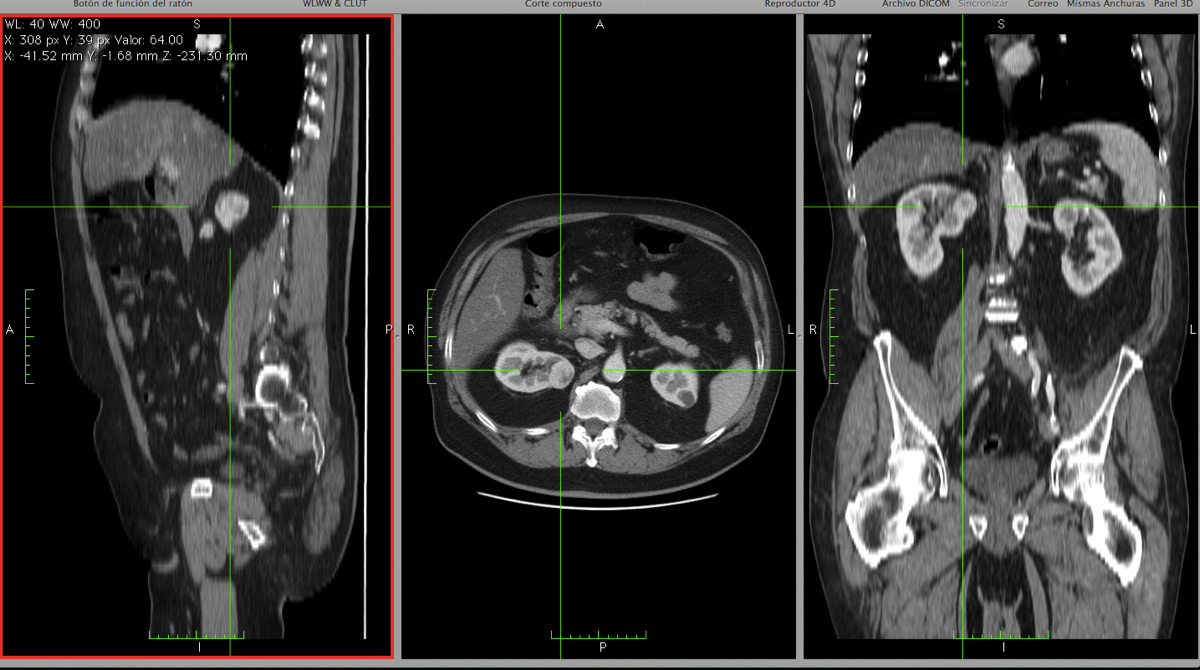

El cáncer de riñón consiste en el crecimiento incontrolado de células tumorales en éste órgano.

El más habitual es el carcinoma de células renales.

Puede curarse si se detecta pronto, pero a menudo da síntomas cuando tiene gran tamaño o se ha extendido a otros órganos.

El cáncer de riñón consiste en el crecimiento incontrolado de células tumorales en éste órgano. El más habitual es el carcinoma de células renales.